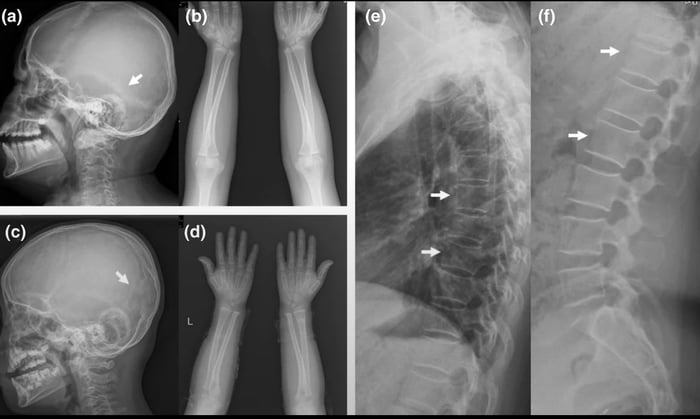

There is a mutation that causes bones to become 8 times denser than normal that allow people to walk away from car accidents without a single fracture but with a trade off of being unable to swim.